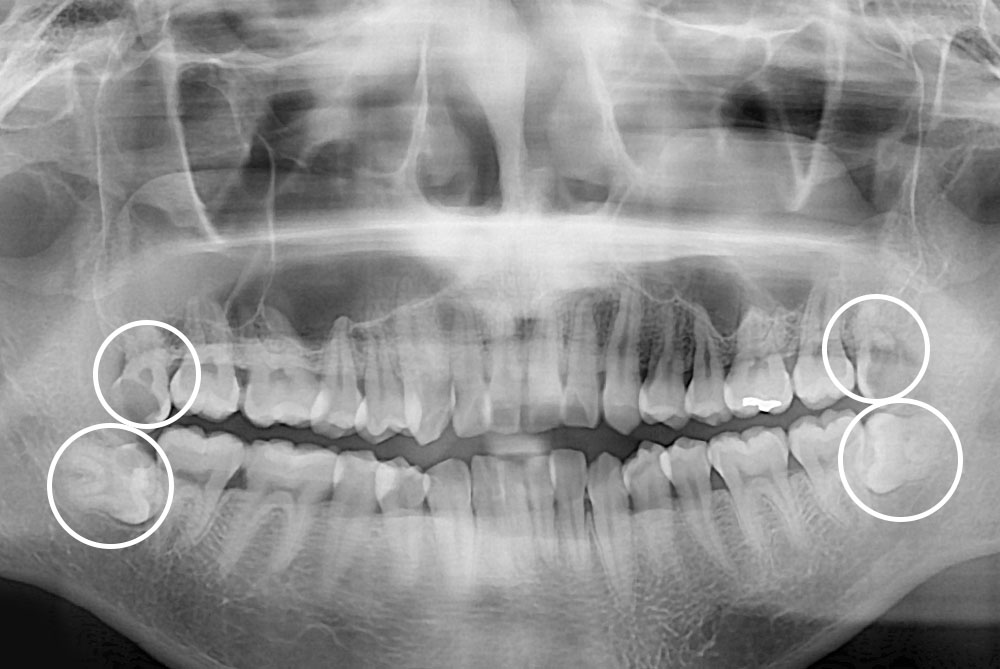

[사랑니] 매복 사랑니 발치

치료전 : 2019-10-10